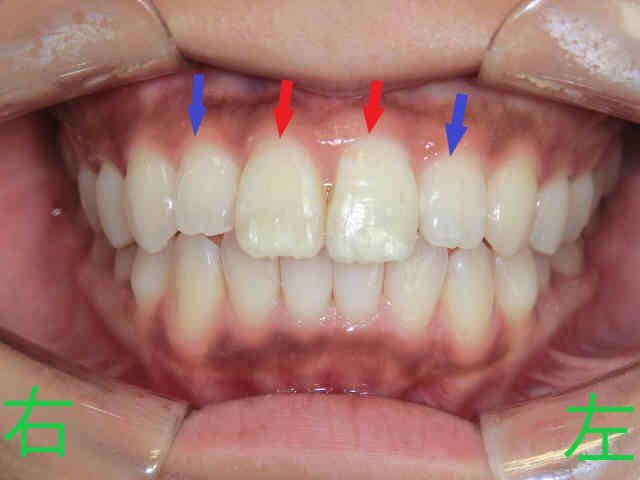

こちらはスマイルトゥルー(アライナー矯正)による治療を開始してから5か月後の口腔内写真です。

上顎左右の中切歯(赤色矢印)に見られた前突感(いわゆる出っ歯)が軽減し、左右側切歯(青色矢印)の逆被蓋(下顎前歯よりも内側に位置していた状態)も改善されています。

治療開始から5か月で、上下顎前歯が接触し、理想的な噛み合わせに近い状態が得られました。